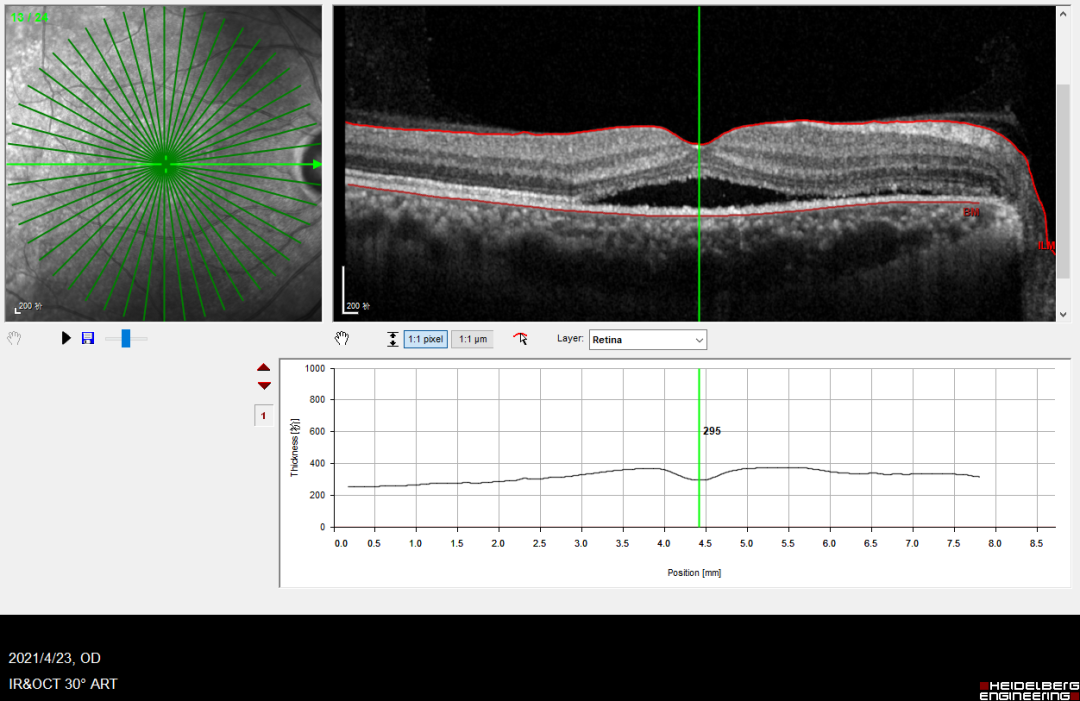

右眼OCT示黄斑水肿,中央黄斑厚度为295μm,中心凹下低反射,考虑为视网膜下液。